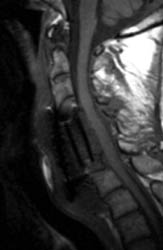

A B C Sagittal T2 FSE (A), sagittal T1 pre (B) and post contrast administration (C) show the graft with blooming artifact where the plate exists anteriorly as well as the screw (lower portion of the image). The susceptibility artifact of the screw shows its ventral positioning essentially outside of the C7 vertebral body. Also, there is T2 hyperintense fluid surrounding the surgical site with the graft material is now surrounded by nonenhancing mixed signal intensity material, predominately hypointense on T1 and hyperintense on T2, possibly suggesting some blood products. There is enhancement in both the anterior and posterior epidural spaces. The distal end of the fixation plate with the screw in the C6 vertebral body appears now displaced anteriorly and there is significant prevertebral soft tissue swelling. Also, this fluid- like material surrounding the bone graft appears to cause some narrowing of the spinal canal, with some mild spinal canal stenosis.